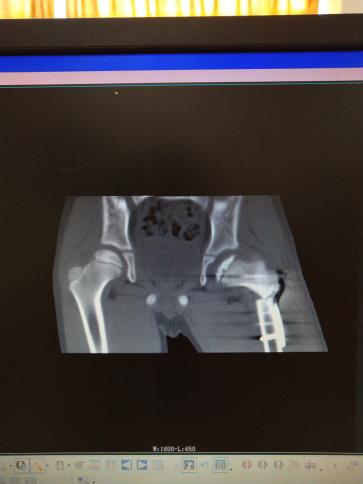

儿童股骨头缺血性坏死

儿童股骨头缺血性坏死行粗隆下内翻截骨钢板内固定治疗,增加股骨头包容,效果满意。图是CT片